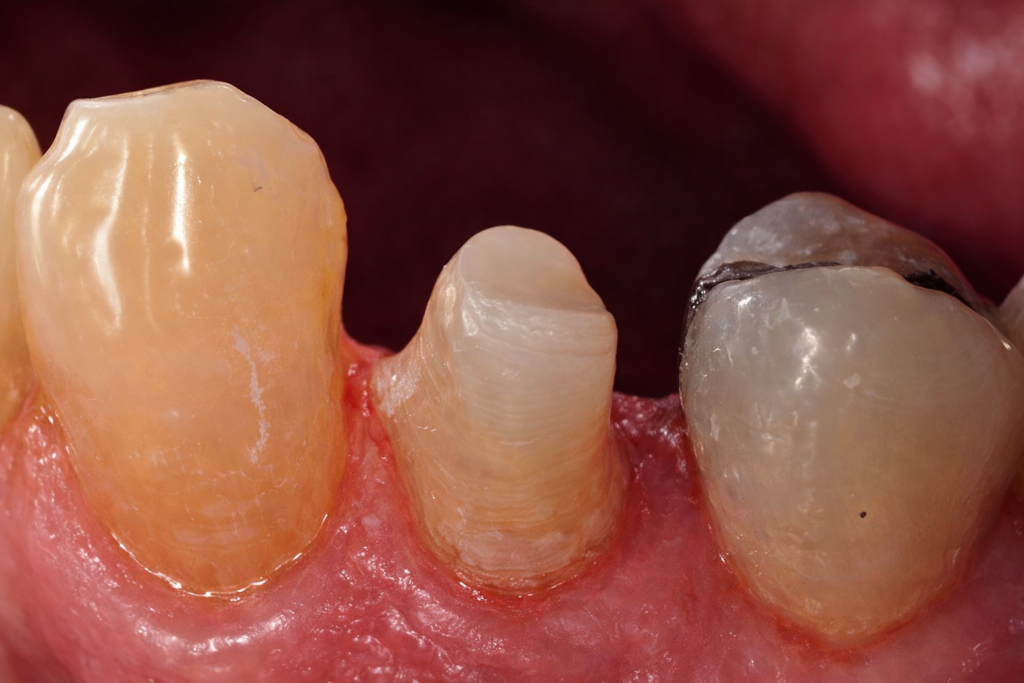

Protocole opératoire de la réalisation d’une reconstitution corono-radiculaire directe avec un tenon fibré et une restauration coronaire au composite

- La radiographie préopératoire :

Elle renseigne sur la morphologie canalaire et permet de déterminer la longueur du logement du tenon et son diamètre, ainsi que la qualité de l’obturation canalaire. - Le champ opératoire :

Reconstitution complexe des dents. - Préparation du logement intra-radiculaire :

Après photopolymérisation finale de la restauration, la préparation coronaire périphérique est achevée avant la pose d’une couronne provisoire.

10-Après photopolymérisation finale de la restauration, la préparation coronaire périphérique est achevée avant la pose d’une couronne provisoire.